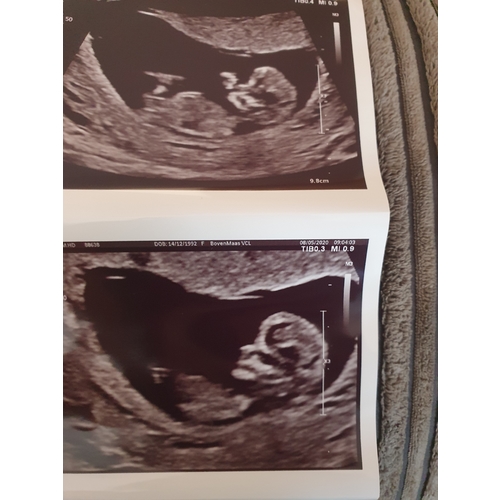

Wat denken jullie meisje of een jongetje.. spannend!

Jongen denk ik, ook de nub馃挋

Wat denk je van mijne ?

Nouja volgens nub test is de kans groot dat jij een meisje krijgt xx

Hahah ik val iedereen lastig met mn foto馃槀 ik wil gewoon zo graag een dochter dat ik het niet kan geloven